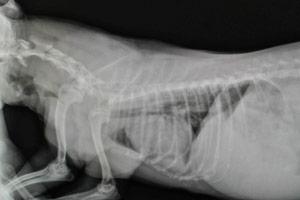

Parmi les tests diagnostiques les plus souvent utilisés, notons la radiographie et la fluoroscopie. La radiographie nous permet de prendre des clichés statiques de la trachée en inspiration et en expiration. La fluoroscopie, quant à elle, est une radiographie « en mouvement » qui permet de constater les changements de la trachée en temps réel. La bronchoscopie (insertion d’une petite caméra dans la trachée et les bronches) est un test diagnostique qui nous permet d’apprécier le grade du collapse de la trachée. Nous utilisons moins souvent ce test puisqu’il présente des dangers lorsque l’animal est en phase aigue.